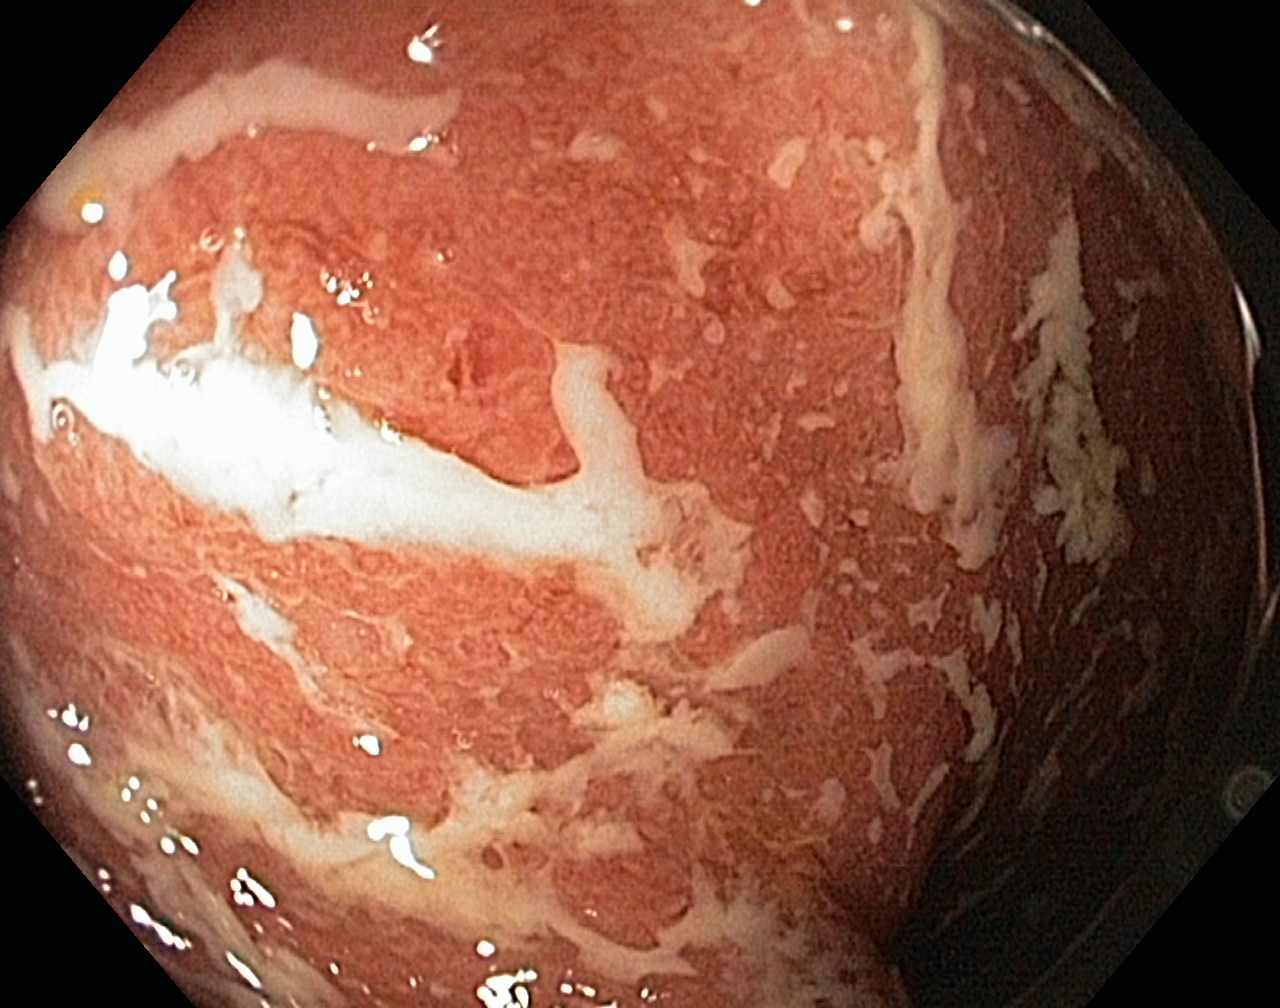

A Distal Ulcerative Colitis